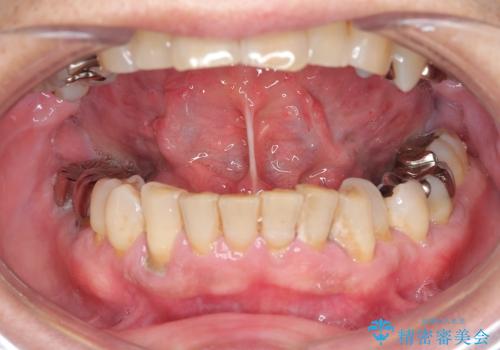

『舌小帯形成術』 ベロの動きを良くして滑舌を改善したい

- 舌の動きが制限され、滑舌を改善したい、と希望され来院されました。

舌小帯形成術を行うことで、滑舌の改善を図ります。形成術は約5分程度で終了し、1週間後に抜糸を行い治療は終了となります。

術後、舌の動きが改善され滑舌の改善を実感することができました。